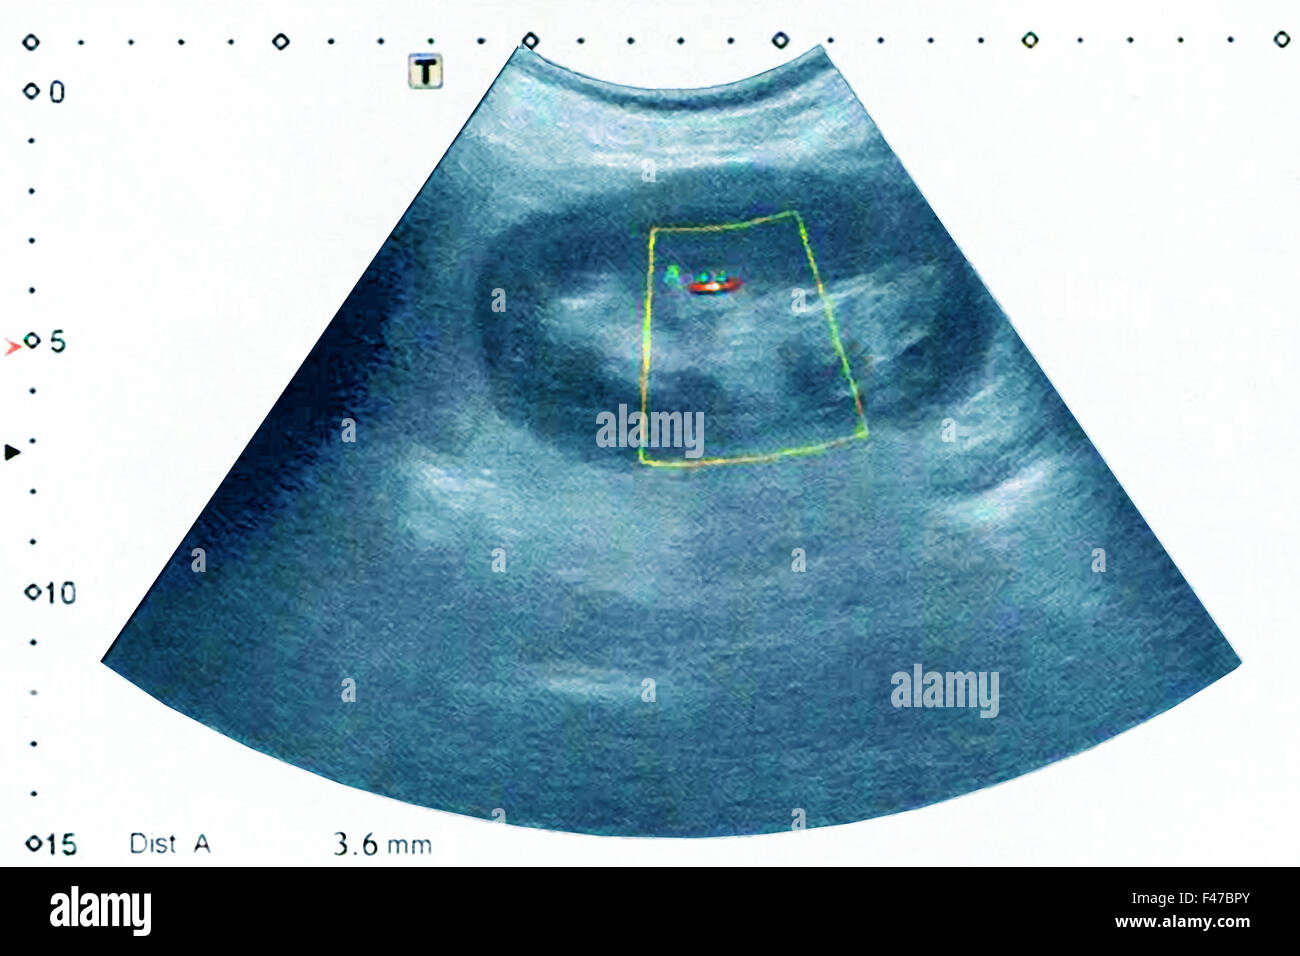

No Radiopaque Lithiasis . Almost no stones with attenuation values of less than 200. kidney stone disease, also known as nephrolithiasis or urolithiasis, is a disorder in which urinary solutes precipitate to form. ultrasound is safe (no risk of radiation), reproducible and inexpensive. It can identify stones located in the calyces, pelvis, and pyeloureteric and vesico. This article reviews types of urinary calculi and their imaging appearances, presents direct and secondary imaging. renal calculi are a common cause of blood in the urine (hematuria) and pain in the abdomen, flank, or groin.

kidney stone disease, also known as nephrolithiasis or urolithiasis, is a disorder in which urinary solutes precipitate to form. renal calculi are a common cause of blood in the urine (hematuria) and pain in the abdomen, flank, or groin. It can identify stones located in the calyces, pelvis, and pyeloureteric and vesico. ultrasound is safe (no risk of radiation), reproducible and inexpensive. Almost no stones with attenuation values of less than 200. This article reviews types of urinary calculi and their imaging appearances, presents direct and secondary imaging.

Lithiasisinduced acute kidney injury Is ultrasonography enough? AJEM No Radiopaque Lithiasis It can identify stones located in the calyces, pelvis, and pyeloureteric and vesico. ultrasound is safe (no risk of radiation), reproducible and inexpensive. renal calculi are a common cause of blood in the urine (hematuria) and pain in the abdomen, flank, or groin. Almost no stones with attenuation values of less than 200. This article reviews types of. No Radiopaque Lithiasis.